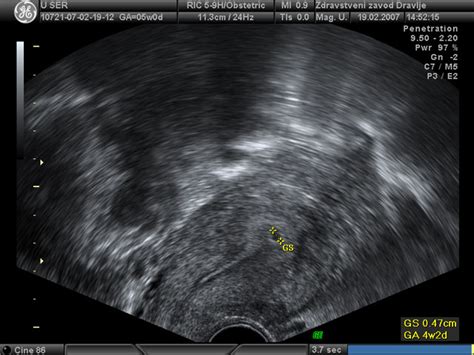

Že v 4. tednu nosečnosti, ob izostanku menstruacije, se lahko na ultrazvoku prikaže gestacijska vrečka. Ta se pojavi kot ehogeni obroč, ki obdaja bistro središče, in raste s hitrostjo približno 1 mm na dan do 9. tedna. Proti koncu 5. tedna gestacijske starosti postane vidna s transvaginalnim ultrazvokom.

Naslednja pomembna struktura, ki postane vidna v 5. tednu nosečnosti, je rumenjak. Ta okrogla struktura, ki oskrbuje zarodek s hranili do razvoja posteljice, zraste do največ 6 mm. Z napredovanjem nosečnosti je s transvaginalnim ultrazvokom pogosto zaznavna srčna aktivnost ploda, še preden je mogoče določiti celično maso. Plodova srčna mišica prične z ritmično kontrakcijo zgodaj, kar se lahko opazi ob robu rumenjaka. Sprva je srčni utrip počasnejši (60-90 utripov/minuto), nato pa se povečuje z razvojem ploda. Včasih utrip ploda ni viden, dokler plod ni dolg vsaj 4 mm.